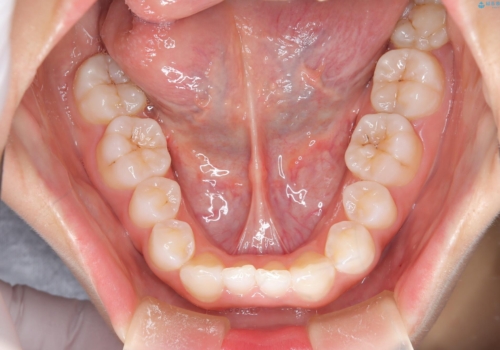

- 子供のころに矯正治療をされていたが、後戻りをしてしまったという20代女性の患者様です。上顎左右の2番が、咬合時に下顎の歯よりも内側に入っているクロスバイトという状態でした。奥歯の咬合関係は変えずに、マウスピース矯正にて前歯の並びを綺麗なアーチに仕上げました。再度後戻りしてしまうリスクを軽減させるために、リテーナー(保定装置)をお渡ししています。